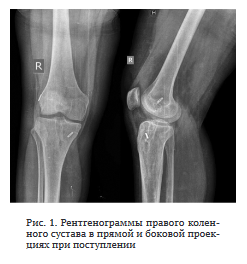

Диагноз: Хронический посттравматический остеомиелит правого бедра и большеберцовой кости. Артрит правого коленного сустава. Состояние после протезирования ПКС правого коленного сустава (рис. 1).

Из анамнеза заболевания: 2010 г. — травма правого коленного сустава, повреждение ПКС, артроскопическое протезирование ПКС. Июнь 2016 г. — повторная травма, лечебно-диагностическая артроскопия с резекцией медиального мениска. Июнь 2021 г. — травма правого коленного сустава с повреждением трансплантата ПКС.

Июль 2021 г. — повторная резекция медиального мениска артроскопически и ревизионное протезирование ПКС, в послеоперационном периоде — гнойный артрит.

Август 2021 г. — дренирование коленного сустава.